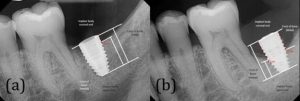

پایه تیتانیومی ایمپلنت دندانی با جراحی مستقیماً درون استخوان فک قرار داده می شود. با گذشت زمان، پست محکم می شود زیرا استخوان اطراف از طریق استئواینتگریشن با آن یکپارچه می شود. این استئواینتگریشن، ریشه طبیعی دندان را تقلید می کند و این امکان را برای ایمپلنت های دندانی فراهم می کند تا زمانی که استخوان فک آن را تثبیت کرد، به طور مستقل بایستد. بنابراین، ایمپلنت های دندانی به حمایت از دندان های اطراف متکی نیستند و راه حلی مستقل برای ترمیم دندان ها ارائه می دهند.

ماندگاری ایمپلنت های دندانی به انسجام استخوانی نسبت داده می شود که درون آن ایمپلنت دندانی با استخوان فک ترکیب می شود. این رابط مستقیم این امکان را برای ایمپلنت فراهم می کند تا به عنوان یک ریشه دندان مصنوعی عمل کند و پایه ای پایدار برای تاج دندان فراهم کند.